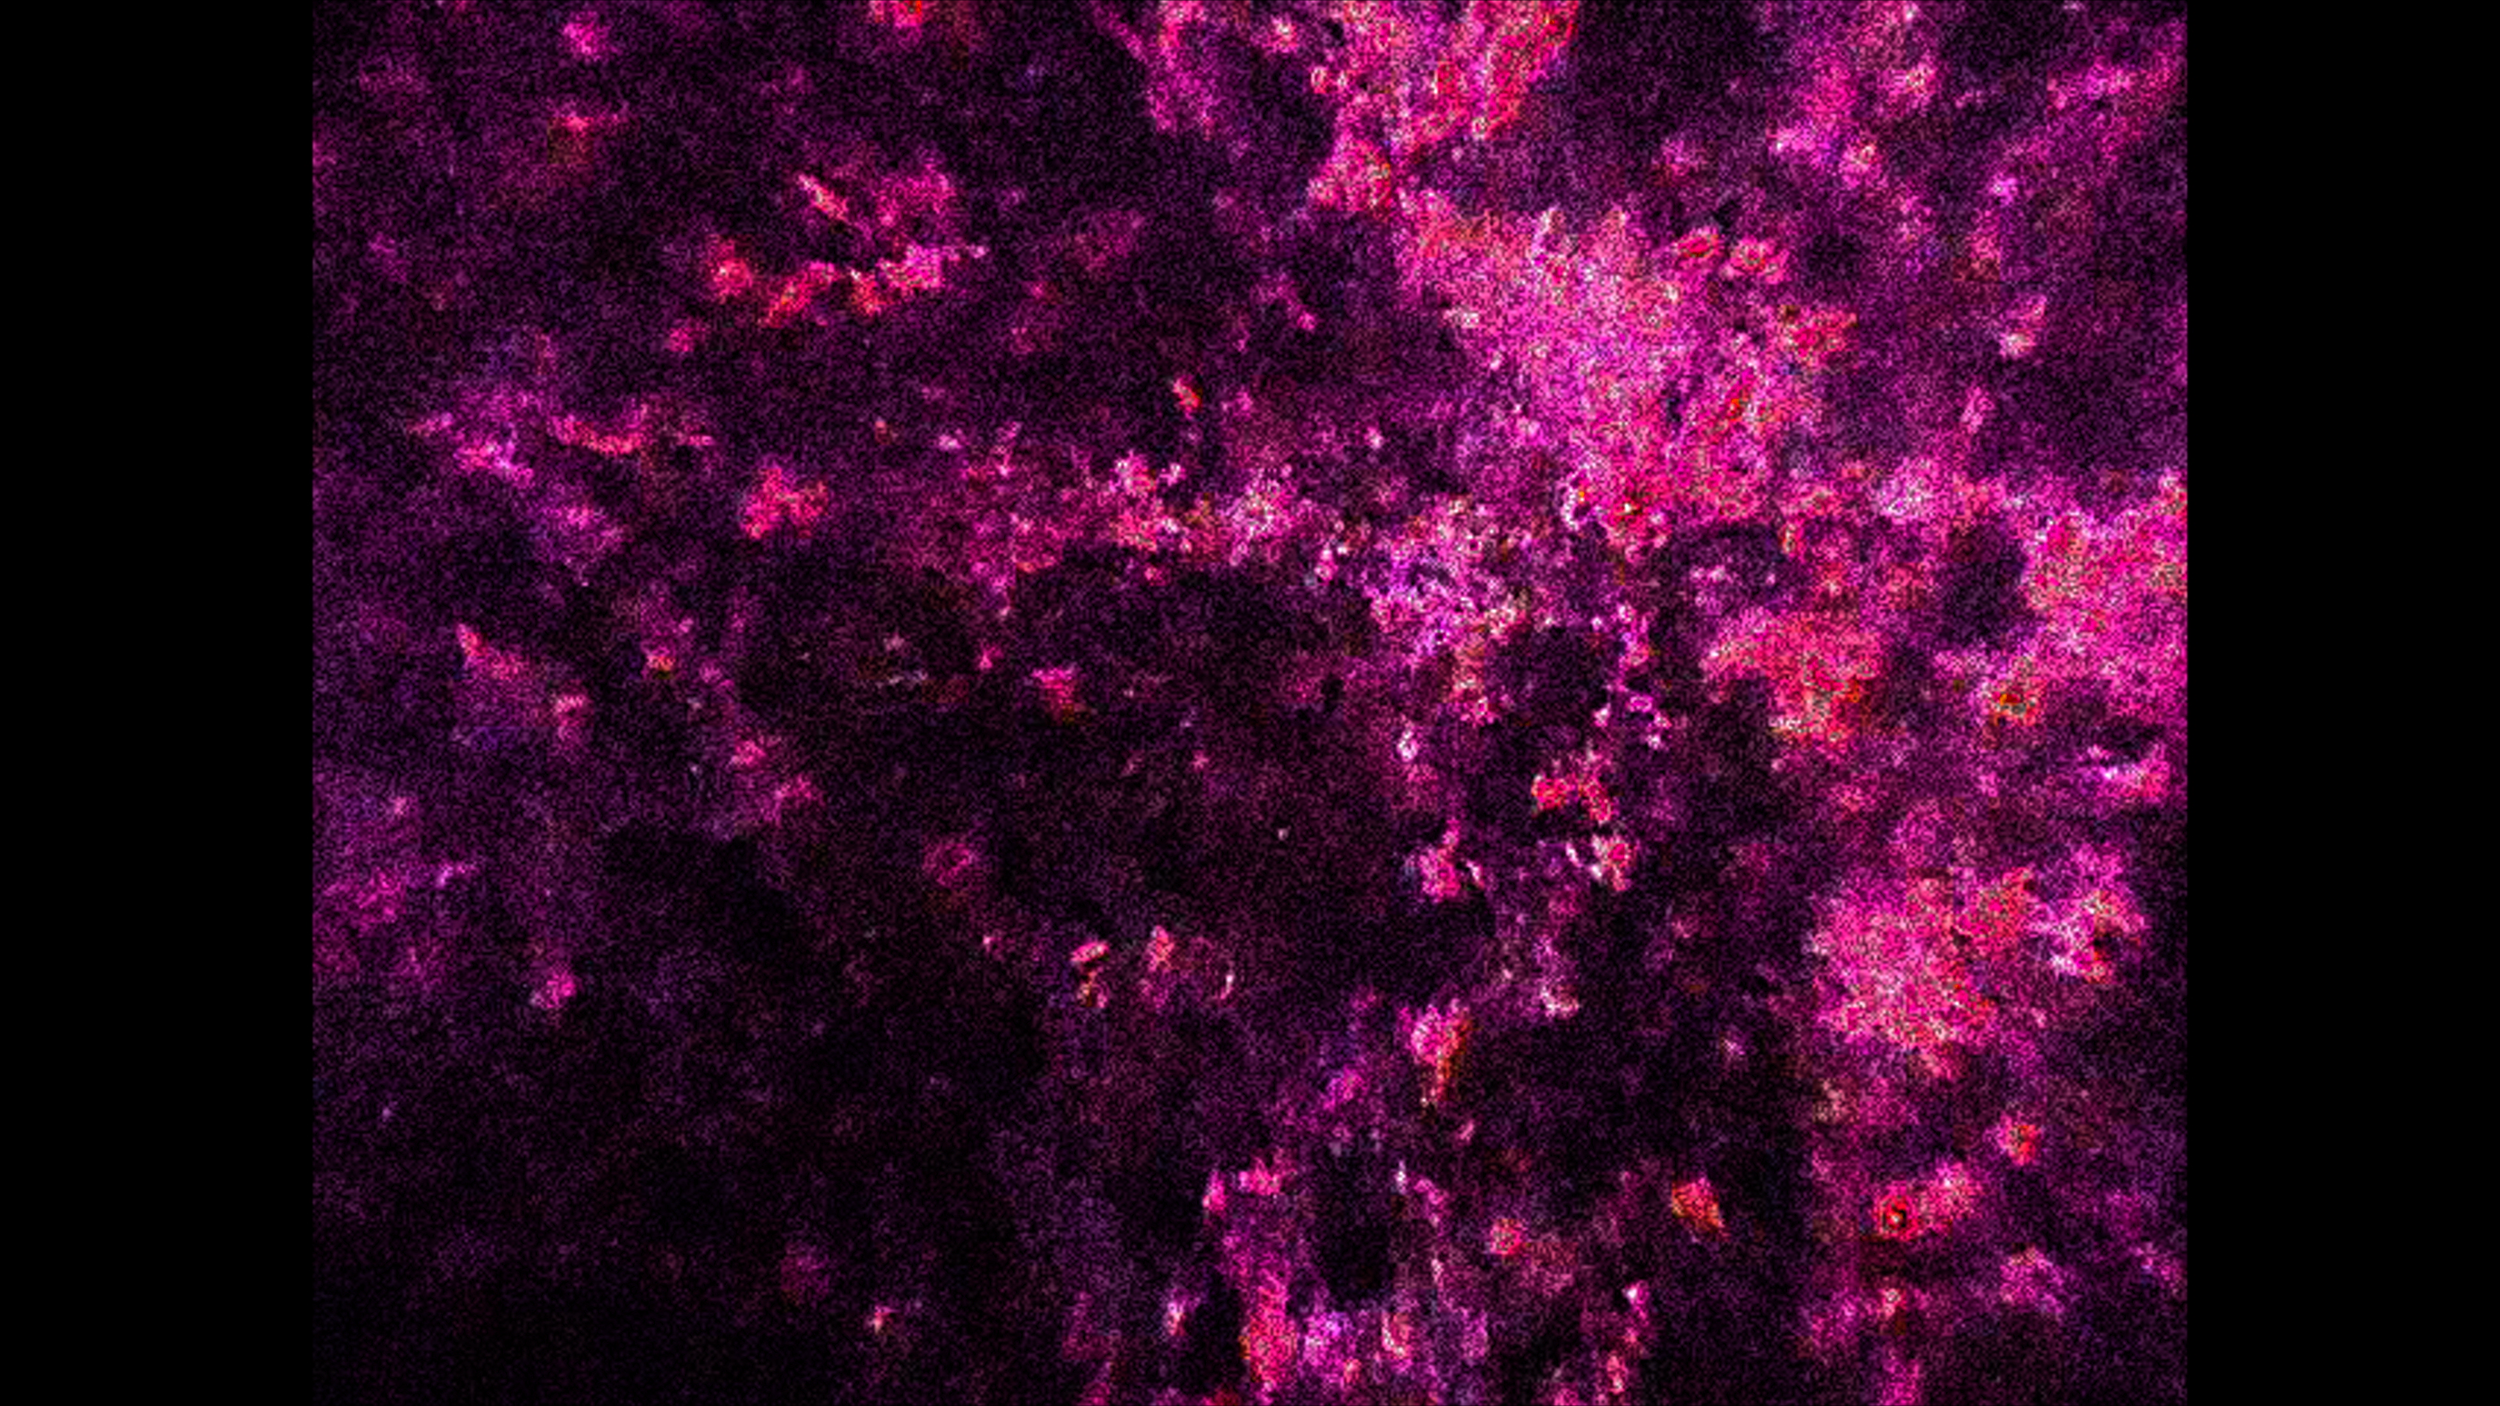

UMRDGM

View Video